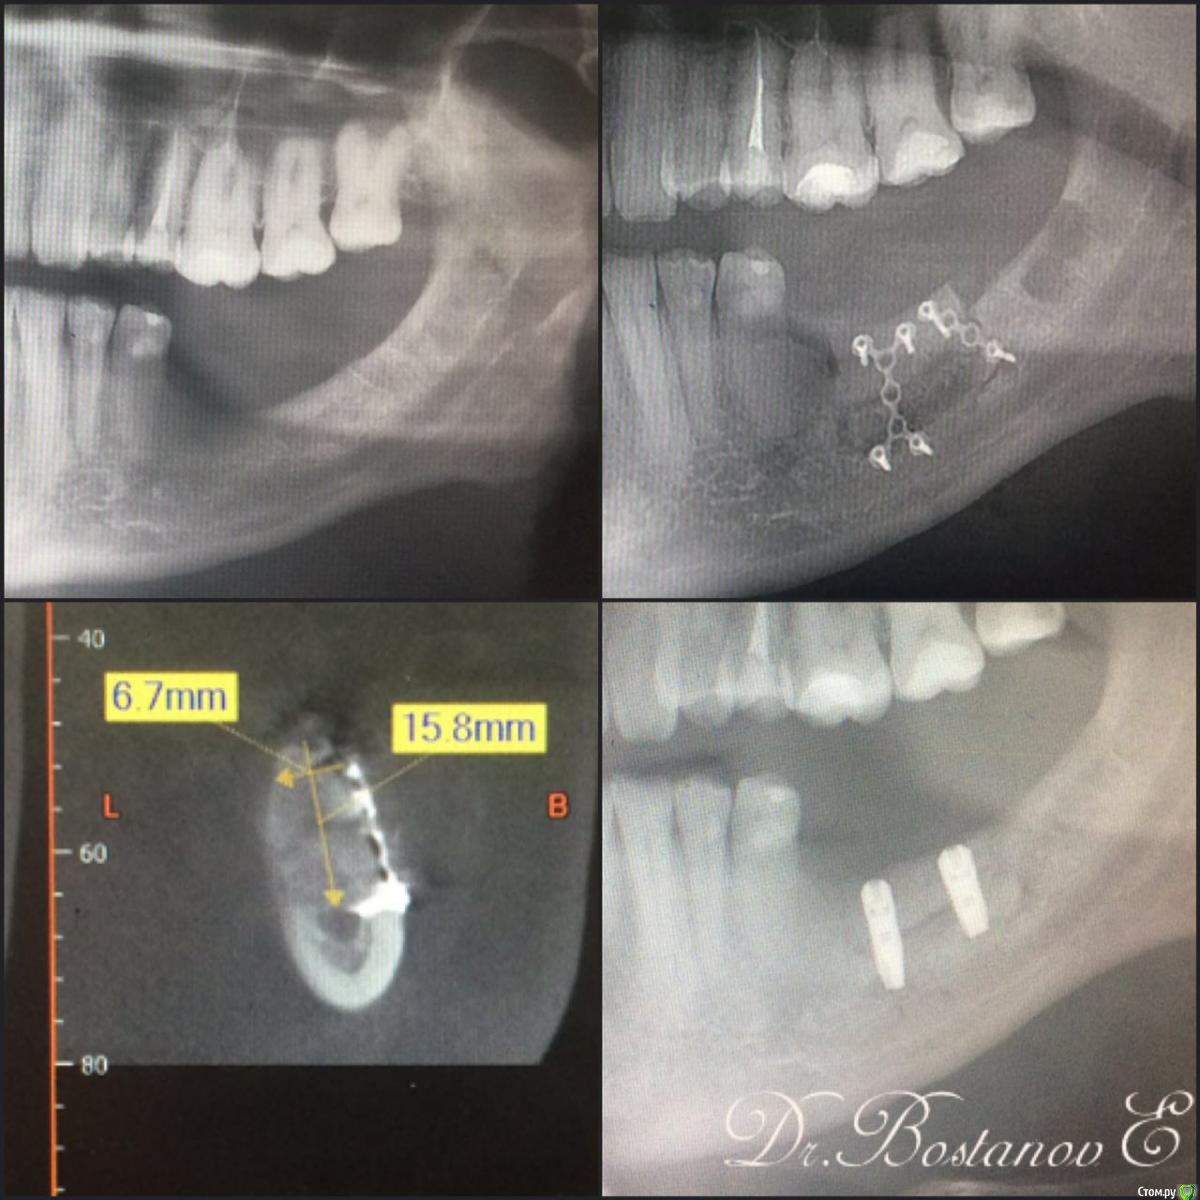

ILGAMSA Опубликовано 8 февраля, 2016 Автор Поделиться Опубликовано 8 февраля, 2016 Вот, кстати... одна из первых крыш. http://s019.radikal.ru/i635/1602/64/11cee0f97d29.png http://s017.radikal.ru/i414/1602/56/aecc99a5bada.png http://s017.radikal.ru/i410/1602/cf/78349eaaa0e5.png Через 4 месяца http://s020.radikal.ru/i717/1602/15/b062388ed059.png И еще через три http://s019.radikal.ru/i607/1602/69/fac3b85c606e.png и кт через 3.5 года http://s018.radikal.ru/i516/1602/cb/3c9299d6ba33.png http://s012.radikal.ru/i319/1602/e8/501e0be4e61a.png 2 Ссылка на комментарий

Larnary Опубликовано 23 июня, 2016 Поделиться Опубликовано 23 июня, 2016 В ноябре мы проводили похожую операцию. Сейчас пациент на этапе протезирования 2 Ссылка на комментарий